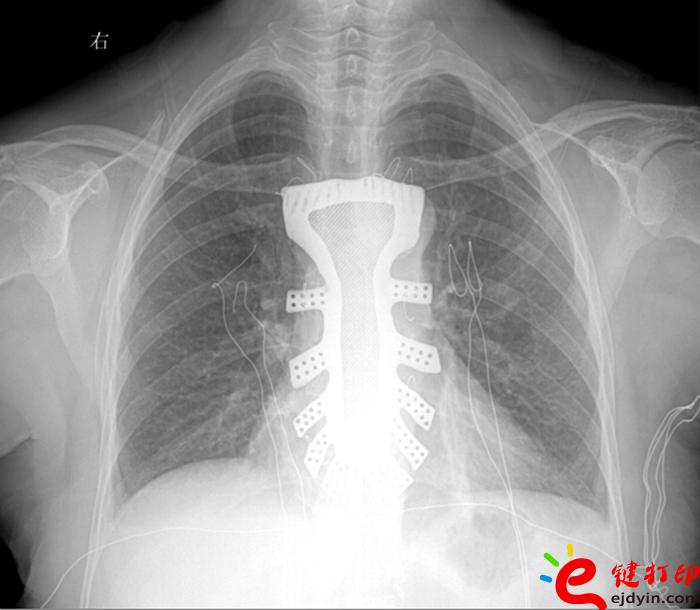

當(dāng)然,“3D打印”的世界遠(yuǎn)不止如此。據(jù)參加大會(huì)的專家和企業(yè)負(fù)責(zé)人介紹,目前“3D打印”已被運(yùn)用在文化創(chuàng)意、文物修復(fù)、生物醫(yī)療、工業(yè)設(shè)計(jì)等多個(gè)領(lǐng)域。如,在航空航天器材上,一些關(guān)鍵零部件采用“3D打印”一次成型,使得其功能更加實(shí)用,重量大幅減少;在醫(yī)療領(lǐng)域,“3D打印”被運(yùn)用于牙齒再造和骨骼修復(fù)等方面,從而使治療更加精準(zhǔn)。